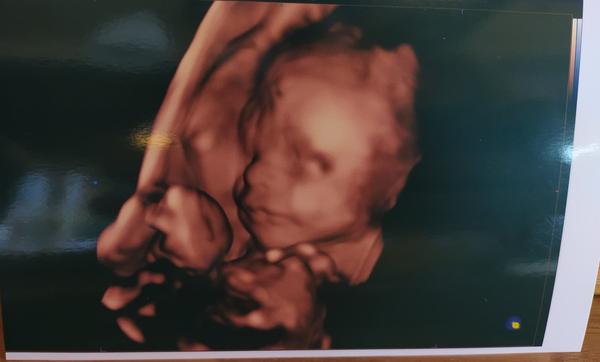

3D a 4D ultrazvuky slúžia viacmenej pre potešenie mamičiek. Tie zároveň nie sú bezplatné a plánované a mamičky si musia za ne priplatiť. Pri 3D ultrazvuku je vidno plod v 3D zobrazení, pri 4D ultrazvuku vidieť navyše aj pohyb bábätka v reálnom čase.

Takéto ultrazvuky je lepšie robiť až po 18. týždní, aby bolo bábätko dostatočne veľké a aby ste z toho mali dostatočný zážitok. Záznam z neho vám môže lekár poskytnúť na CD, aby ste mali na svojho drobčeka pamiatku, ako vyzeral ešte v brušku.